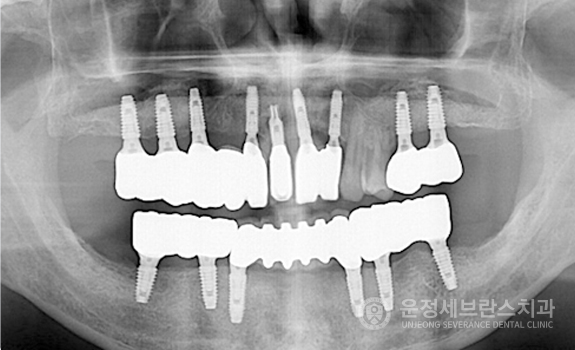

임플란트를 다시 식립해야 하는 환자의 고민. 그리고 1차 수술에 비해 난도 있는 정교한 재수술.

재수술은 까다롭기 때문에 의료진의 실력이 가장 중요합니다. 정확한 검사를 바탕으로 원칙을 지키는 식립 도와드리겠습니다.